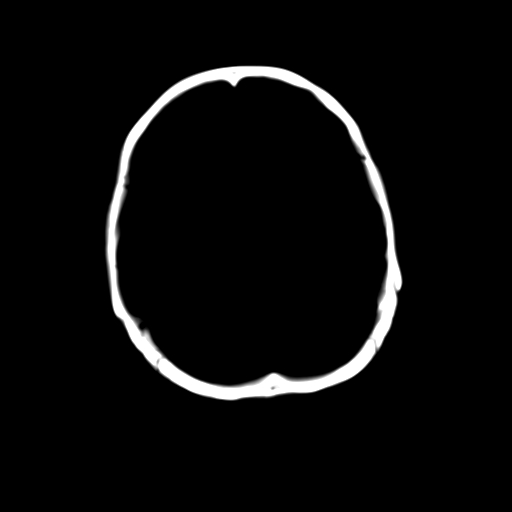

女,42岁,前额部外伤1小时,伤后头痛。

头颅ct平扫未见异常

未见明显异常!

颅脑ct平扫未见异常,必要时复查

未见明显外伤性改变。

左枕骨松质骨不均匀低密度灶,边缘清楚,考虑良性松质骨性骨瘤可能性大。